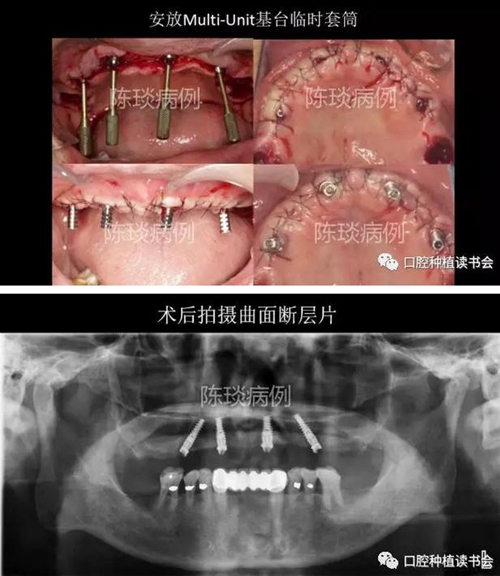

5,種植外科流程:

(1)數字化導板引導下完成種植體植入。

8.jpg

9.jpg

10.jpg

(2) 種植體植入術后制作臨時修復體即刻修復。

11.jpg

12.jpg

13.jpg